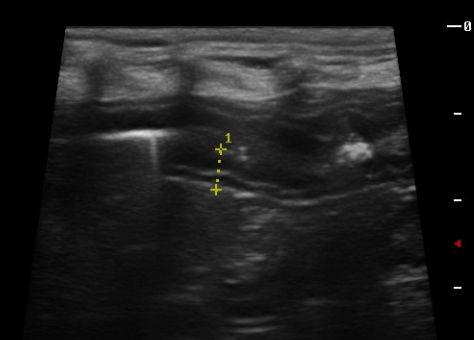

선천성 문맥전신단락(Portosystemic Shunt, PSS)은 태생기 혈관 발달 이상으로 문맥혈이 간을 거치지 않고 전신 순환으로 유입되는 질환입니다. 병태생리는 교과서적으로 명확하지만, 실제 임상 현장에서는 특히 어린 강아지에서 진단이 지연되는 대표적인 질환입니다. 이는 질환이 희귀해서라기보다, 임상 증상이 지나치게 비특이적이며 ‘질병’이 아닌 단순한 ‘성장 문제’나 ‘기질적 특성’으로 해석되기 쉽기 때문입니다.

선천성 PSS는 단순한 혈관 기형에 그치지 않습니다. 문맥혈이 간을 우회함으로써, 간 실질은 정상적인 혈류 자극과 영양 공급, 즉 hepatotrophic factors를 충분히 받지 못하고, 그 결과 이차적인 간 저형성(hypoplasia)에 이르게 됩니다. 다시 말해, 문제는 ‘우회하는 혈관’뿐 아니라 ‘기능적으로 성장하지 못한 간’ 그 자체에 있습니다.